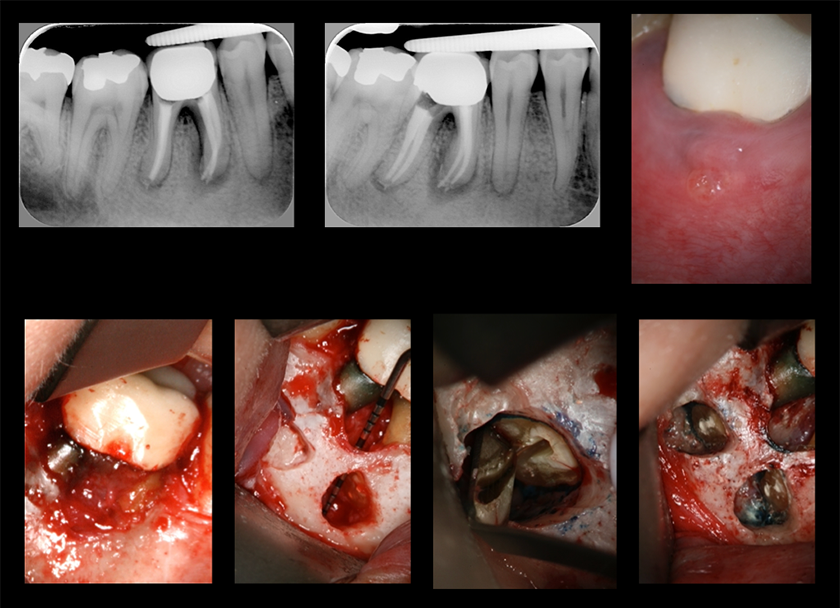

エンド・ペリオ病変

LIVE配信 2026年7月22日(水) 19:30~21:00

見逃し配信:2026年7月29日(水)~8月7日(金)

講演のポイント

・エンド・ペリオ病変の病態を理解する

・エンド・ペリオ病変の治療介入のタイミングについて理解する

・臨床におけるエンド・ペリオ病変の取り扱いや意思決定における重要事項を知る